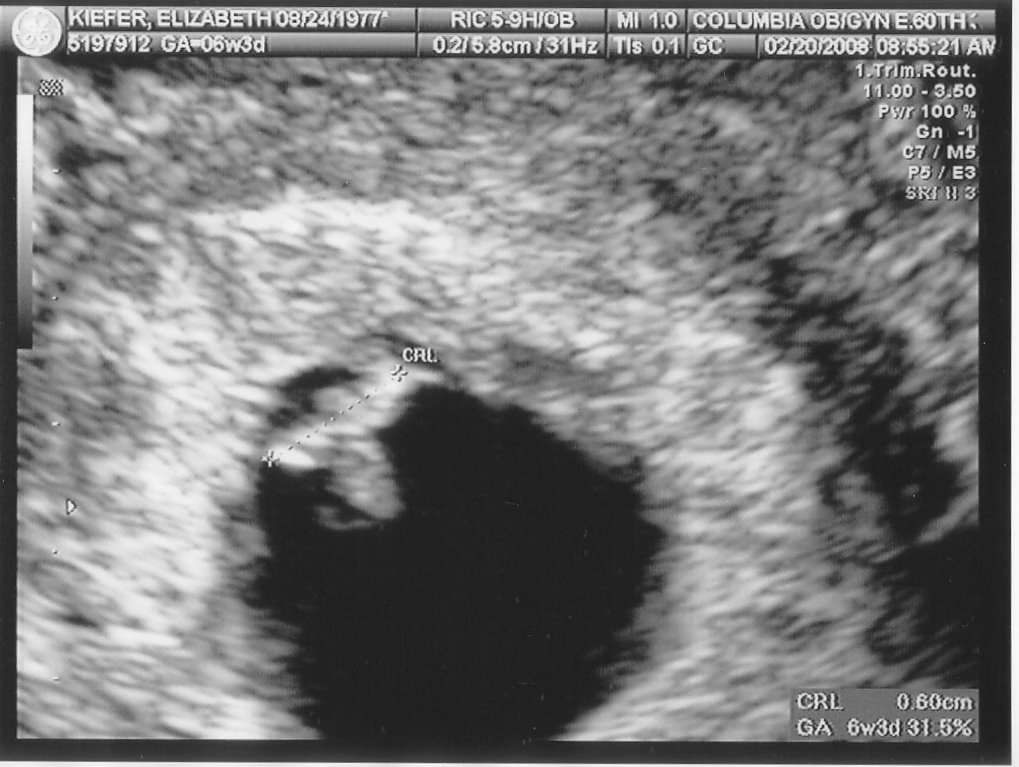

On Friday we headed uptown for our second ultrasound. Nobody told me that baby m0ves around in there at 12 weeks (thanks for the help, parenting books, keep up the good work!), so I just about freaked out when he arched his back and rubbed his face (or she/her, of course, we don’t find that out for another 6 weeks). Fortunately our tech was used to people gasping loudly. Sooooo cool.

In case you were wondering if I was going to be a stereotype of a dad, I’m including all 5 blurry blob pictures here. And if I had an hour long movie of same, I’d post that, too.